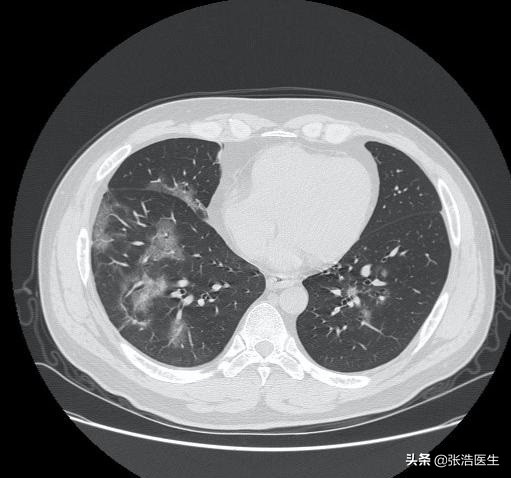

(上图是冠状病毒肺炎的胸部CT图像)

就目前公布的情况来看,单纯的从发热症状来看,无法完全的区别的新型肺炎和其他的肺炎,建议出现咳嗽、呼吸困难、发热症状的人群,尤其是有武汉接触史的,尽早上报隔离,必要时就诊发热门诊及时治疗,为自己考虑也为周围的人考虑。#疫情之下,我的日常生活# #关注新型肺炎# #清风计划# @清风计划 @头条健康